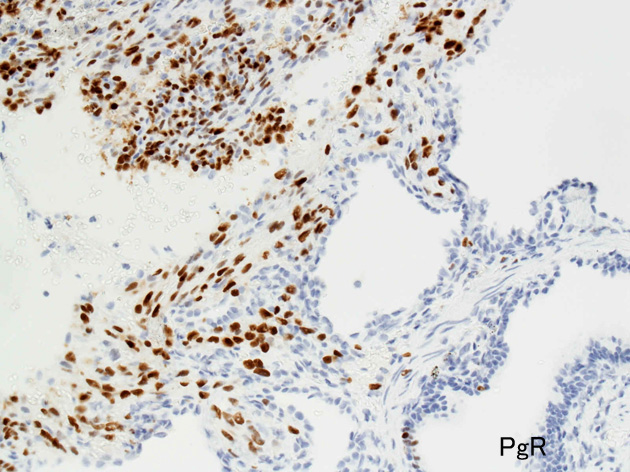

LAMの肺病変

嚢胞周囲または肺血管, リンパ管, 細気管支にそうLAM cellの浸潤, 集簇を特徴とする。LAM cellには2種類が認められ, 小型紡錘形細胞と細胞質の豊富な類上皮様細胞があり, 紡錘型は主に集簇巣の中心に存在し増殖能が高い。 類上皮様LAM cellは辺縁部に多く, 増殖能は低いがHMB45を強く発現している。

LAM cellの免疫染色--SMA, desmin, vimentin(vimentinはいつも陽性とはならない)が陽性となりmuscle lineageであるが典型的な筋細胞と異なり,

免疫染色